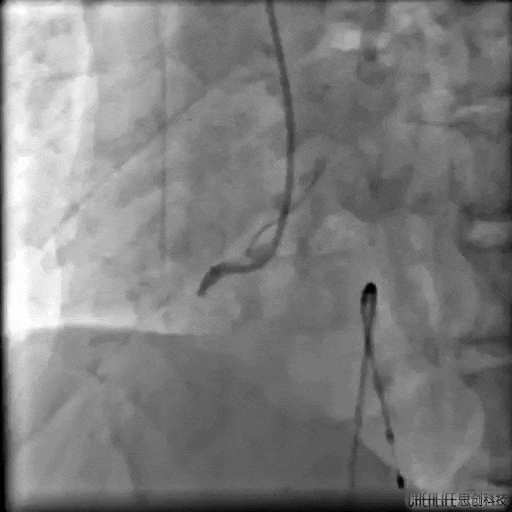

治疗前 宫兆滨主任指挥手术团队,迅速为张先生安装临时起搏器。随着起搏器开始工作,患者血压持续攀升到正常值,心率也从危险的30次/分稳步提升至80次/分,手术条件终于具备!随后,手术团队精准操作,成功打通了张先生阻塞的血管。整个过程历时约40分钟,这场急诊心血管介入手术宣告成功!